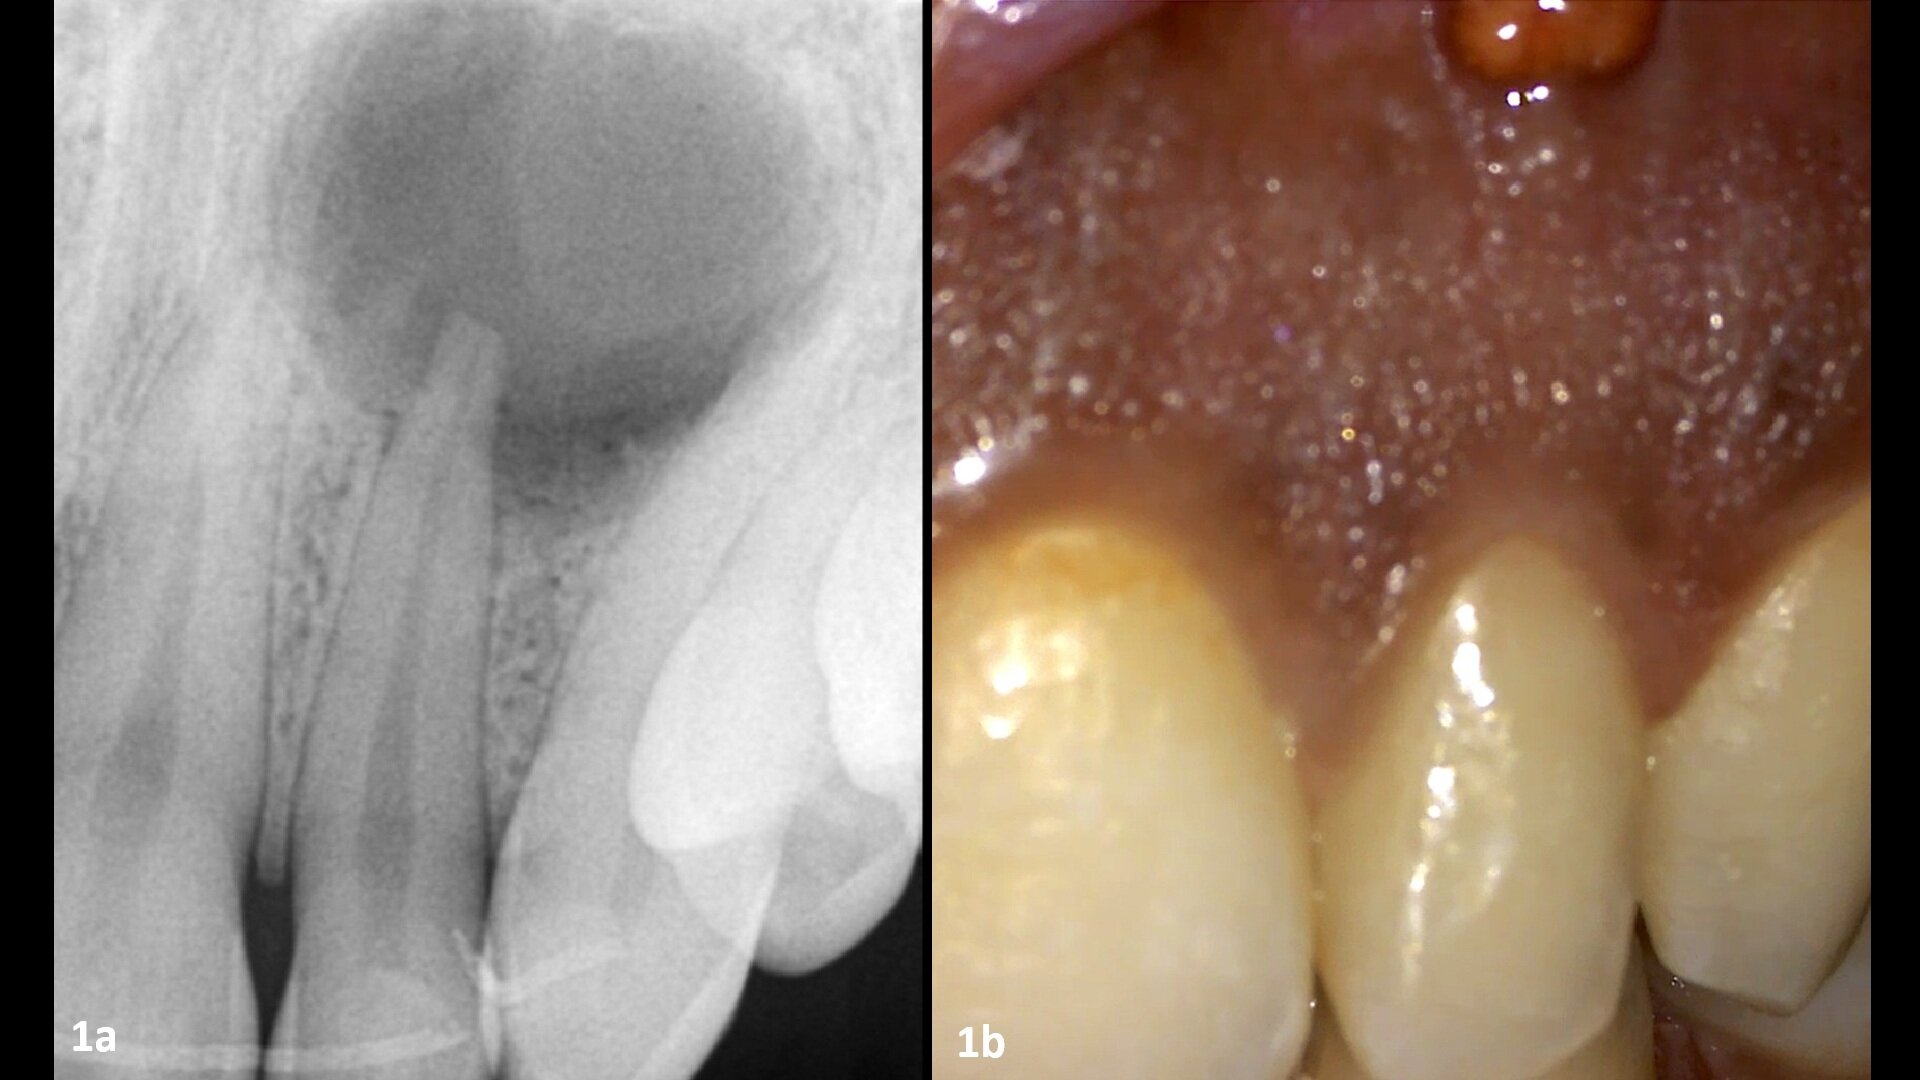

Figs. 1a & b: Fistula in the area of the bone above the lateral incisor (a). Large lesion above the lateral incisor (b). (All images: Dr Philippe Sleiman)

The patient presented for assessment of a fistula in the anterior maxilla on a radiograph, appearing as a large lesion above the lateral incisor (Fig. 1). The patient recalled having been hit by a ball a long time before. A CBCT scan was taken, and it showed a large cystic lesion destroying a large portion of the anterior maxilla. Owing to the edge-enhancing capability of the DTX software provided by artificial intelligence, we can enhance the quality of the image. Since the CBCT scan was taken in a different centre, we imported the DICOM file into the DTX software. The image clearly showed the nerve entering the central incisor and a thin layer of bone covering the apex, and the nerve and periodontal ligament in this area were intact (Fig. 2).